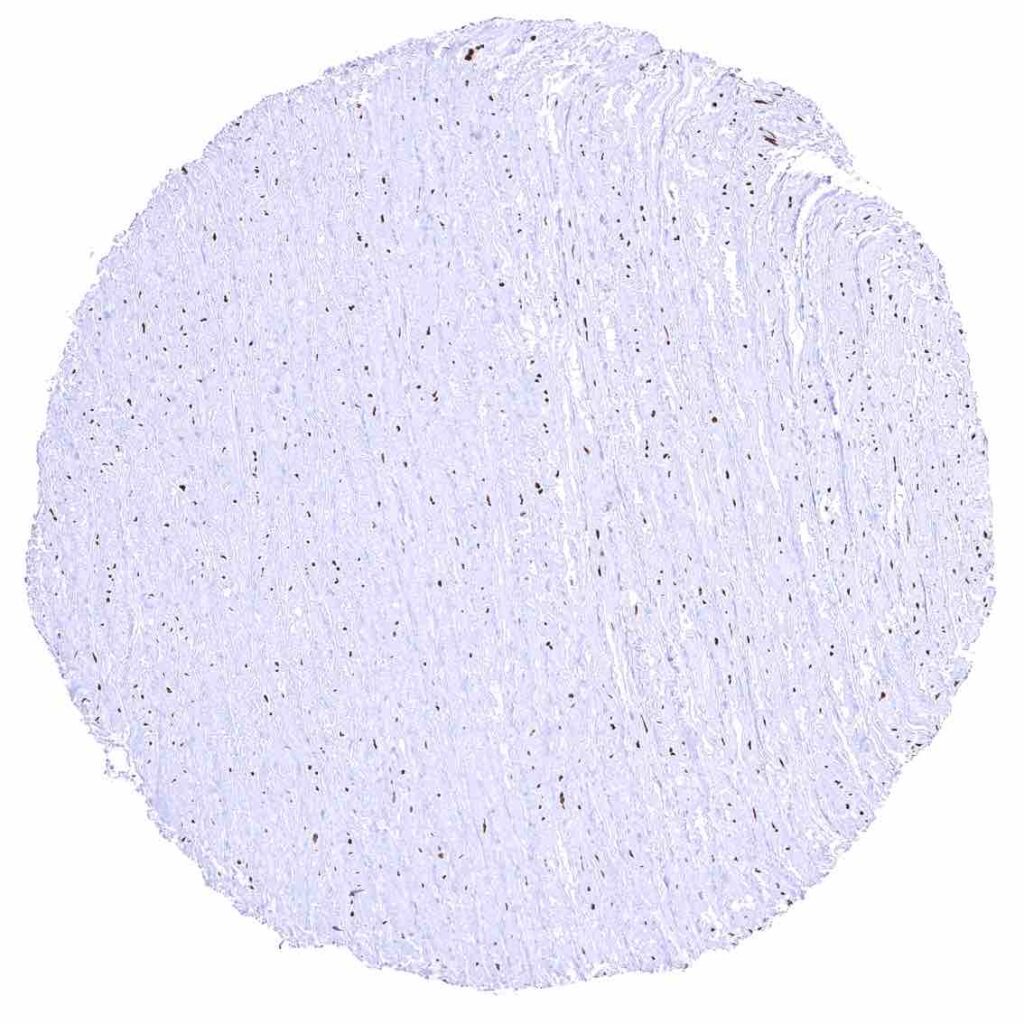

Aorta, media – Strong nuclear p27 staining of muscle cells in the aorta.